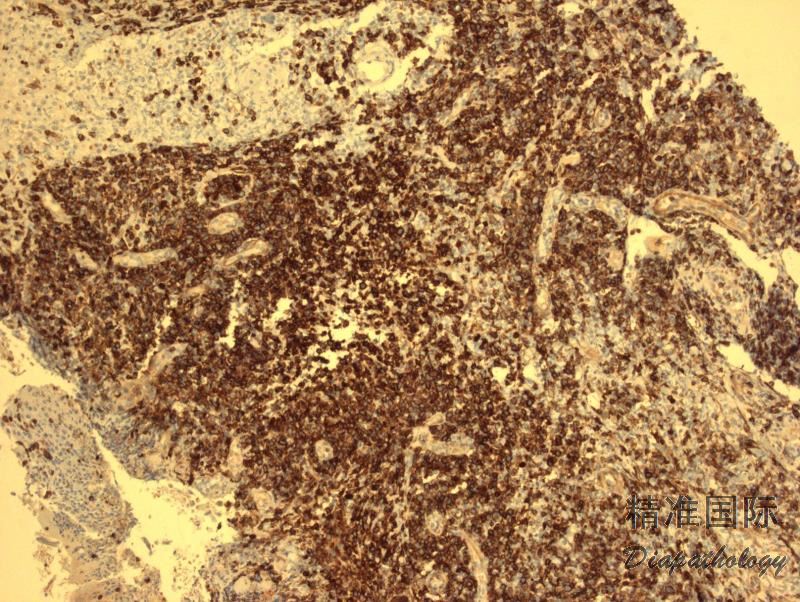

低倍镜下,真皮病变区域多为楔形,但组织形态变异很大,部分是由于反映了病变的不同阶段。目前分为至少 6 种亚型。A 型:最常见(>80%)。散在的 CD30+异形单核、多核或 HRS 样大细胞混合于大量炎性背景细胞(小淋巴细胞、组织细胞、中性和嗜酸性粒细胞)。B 型:少见(<5%)。中小异型淋巴细胞(CD30+/-),含不规则和或脑回样核,呈现亲表皮侵润,与 MF 类似。C 型(约 10%):大异形细胞成片状侵润(CD30+),背景可有少量炎性细胞,此型与 C-ALCL 类似。 D 型(<5%):中小异形淋巴细胞强亲表皮性侵润,表达 CD8 和 CD30,类似原发性皮肤 CD8+侵袭性亲表皮细胞毒 T 细胞淋巴瘤。E 型(<5%):中小异形、多形性细胞(CD8+、CD30+)呈现血管中心性、血管破坏性浸润伴出血、坏死,临床表现为斑块结节病变,并很快形成溃疡,进而变成大的坏死结痂病灶。LyP 伴 6p25.3 重排(<5%):此型特征是有 DUSP22-IRF4 易位,组织学见中小异形脑回样核细胞(CD30 弱+)亲表皮浸润,伴中到大细胞(CD30 强+)真皮层浸润,类似 MF 大细胞转化。此外,还有其它罕见类型,如亲毛囊型、肉芽肿样型等。同一病例可以同时存在不同的组织学亚型。认识这些不同的亚型可以避免过度诊断为 T 细胞肿瘤。

免疫表型:大异形肿瘤细胞(A,C 型)表达 CD30 和细胞毒分子,常表达 CD4,但其它 T 细胞相关抗原常阴性。 B 型肿瘤细胞表达 CD3 和 CD4,但不表达 CD30 和 CD8。 D 和 E 型肿瘤细胞表达 CD30. CD3. CD8,不表达 CD4。DUSP22-IRF4 病例表达 CD8 或 CD4/CD8 双阴性,CD30 弱或强阳性。所有亚型都不表达 ALK,EMA 一般也阴性,有个 1 别报道表达 CD56。